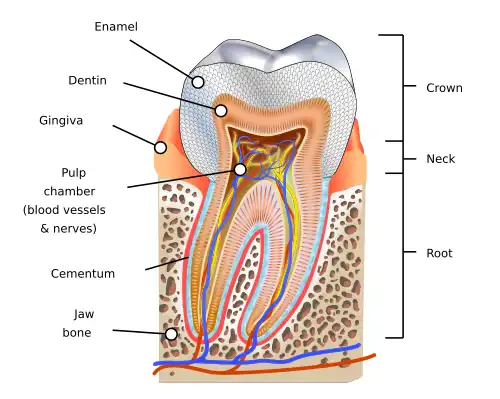

Regenerative medicine has been studied by dentists to find ways that damaged teeth can be repaired and restored to obtain natural structure and function.[42] Dental tissues are often damaged due to tooth decay, and are often deemed to be irreplaceable except by synthetic or metal dental fillings or crowns, which requires further damage to be done to the teeth by drilling into them to prevent the loss of an entire tooth.

Researchers from King's College London have created a drug called Tideglusib that claims to have the ability to regrow dentin, the second layer of the tooth beneath the enamel which encases and protects the pulp (often referred to as the nerve).[43]

Animal studies conducted on mice in Japan in 2007 show great possibilities in regenerating an entire tooth. Some mice had a tooth extracted and the cells from bioengineered tooth germs were implanted into them and allowed to grow. The result were perfectly functioning and healthy teeth, complete with all three layers, as well as roots. These teeth also had the necessary ligaments to stay rooted in its socket and allow for natural shifting. They contrast with traditional dental implants, which are restricted to one spot as they are drilled into the jawbone.[44][45]

A person's baby teeth are known to contain stem cells that can be used for regeneration of the dental pulp after a root canal treatment or injury. These cells can also be used to repair damage from periodontitis, an advanced form of gum disease that causes bone loss and severe gum recession. Research is still being done to see if these stem cells are viable enough to grow into completely new teeth. Some parents even opt to keep their children's baby teeth in special storage with the thought that, when older, the children could use the stem cells within them to treat a condition.[46][47]